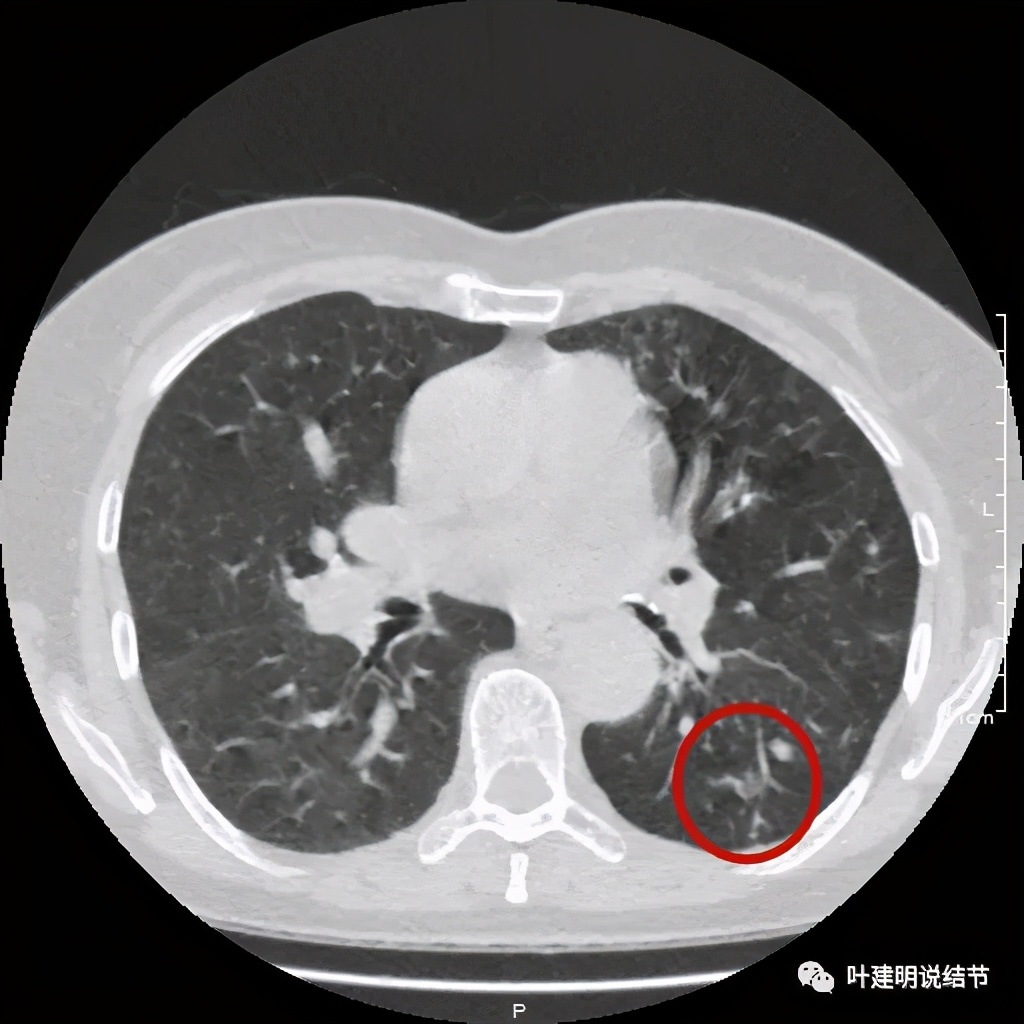

金华的某A,女性,56岁,去年8月份检查发现左肺下叶结节,是实性的,还中间有个空洞,我们说若磨玻璃结节伴空泡或空腔多为恶性范畴的,实性的也是可能性会大一些,但不如磨玻璃确切,因为结核、感染等也会类似的。我们先来看她当时的CT图像:

左下结节与血管关系密切,此层似磨玻璃结节,还夹在小血管之间,其中有血管紧贴病灶,略迂曲